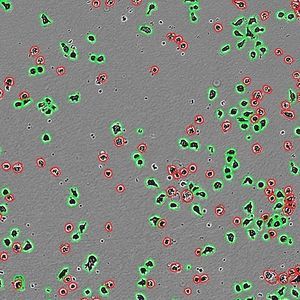

... artificial (IA), sin necesidad de etiquetas. El software de análisis de la salud celular Incucyte® AI proporciona un potente flujo de trabajo que apoya a todo su equipo de investigación. El módulo de ...

Sartorius Group